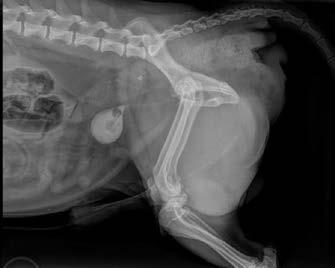

Ultrasonography of the right perineal swelling revealed a fluid-filled object, suspected to be the urinary bladder, herniated through the pelvic diaphragm. Faecal matter was also apparent on ultrasound. Orthogonal survey abdominal radiography was performed. A urethral catheter was placed, and positive contrast cystography performed by instilling 5mL of contrast media (Urografin®; Bayer Australia Ltd, Pymble NSW, 2073, Australia) into the urinary catheter. Repeat orthogonal radiography confirmed urinary bladder retroflexion (Figure 1a). The bladder was then manually reduced into an appropriate anatomical position (Figure 1b). Due to the severity of the deficit, the bladder was unable to remain

Figure 1. Lateral abdominal radiography following positive contrast cystography identifying urinary bladder retroflexion (a). The bladder was then manually reduced into an appropriate anatomical position (b).